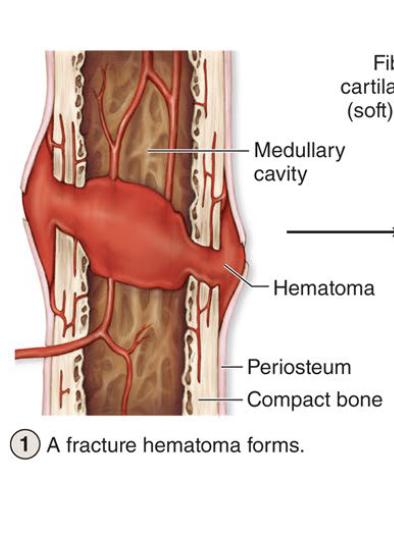

Bone Fracture Repair

Hematoma forms

Fibrocartilagenous callus forms

Hard (bony) callus form

Bone remodel

Hematoma Forms

First step to fracture repair

Clotted blood form at fracture site

Fibrocartilagenous Callus Forms

Second step to fracture repair (take at least 3 weeks)

Soft callus of collagen & cartilage bridge the broken bone

Hard (Bony) Callus Form

Third step to fracture repair (several months)

Soft callus replace with spongy bone

Bone Remodel

Last step to fracture repair (3-4 months, longest step)

Osteoclasts remove excess bony material from outer & inner surfaces. Bones regains its original shape & strength